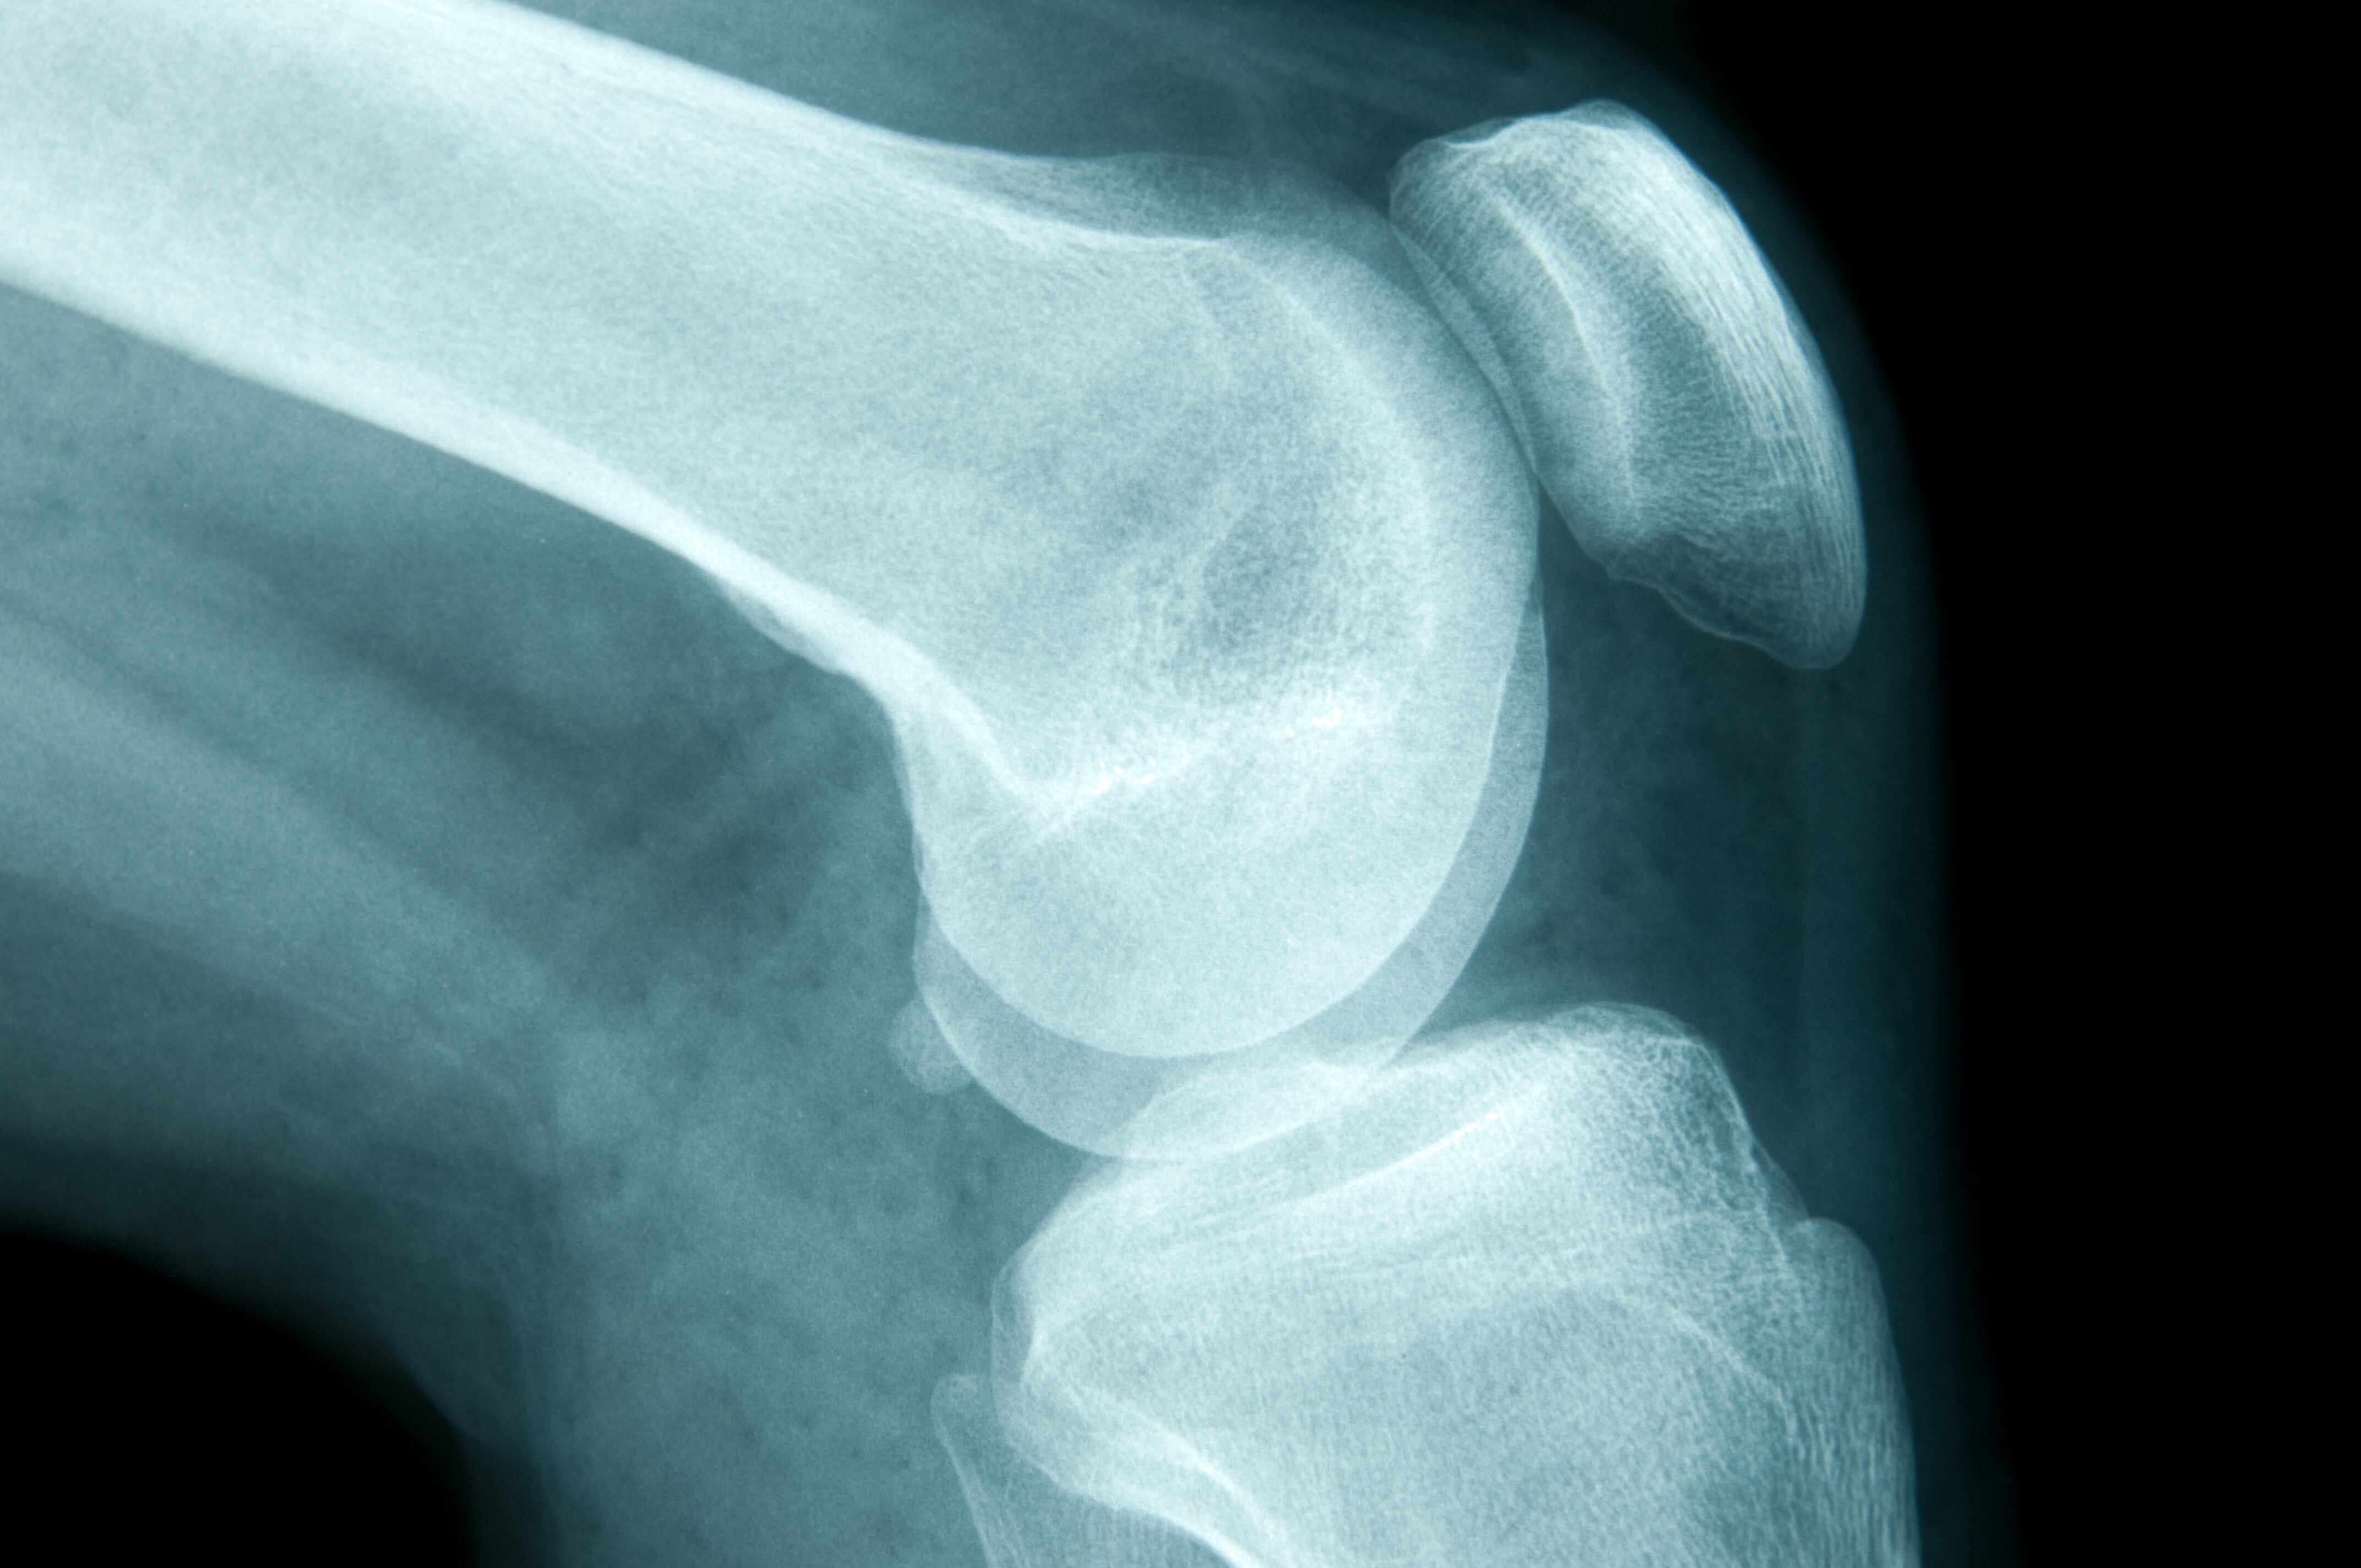

El dolor fue tan intenso que decidió asistir al médico, ya que además estaba acompañado con una gran inflamación de su articulación izquierda, lo que provocó que aumentara su temor por lo que estaba padeciendo. En el hospital fue sometida a una serie de exámenes por parte de su médico de cabecera, que le informó que presentaba una bursitis en esa rodilla.

Mayo Clinic, portal especializado de salud, explica que la bursitis es la inflamación de un saco pequeño lleno de líquido ubicado cerca de la articulación de la rodilla. “La bolsa reduce la fricción y amortigua los puntos de presión entre los huesos y los tendones, los músculos y la piel que están cerca de las articulaciones”, indica el portal.

La joven explicó que no tenía bursitis sino que los nuevos exámenes revelaron que en verdad el dolor en la rodilla era provocado por un tumor agresivo que necesitaba ser atendido de manera inmediata.

En verdad lo que tenía era osteosarcoma, un tipo de cáncer de hueso y que se encuentra con mayor frecuencia en los huesos largos, más a menudo en las piernas, pero puede comenzar en cualquier hueso.